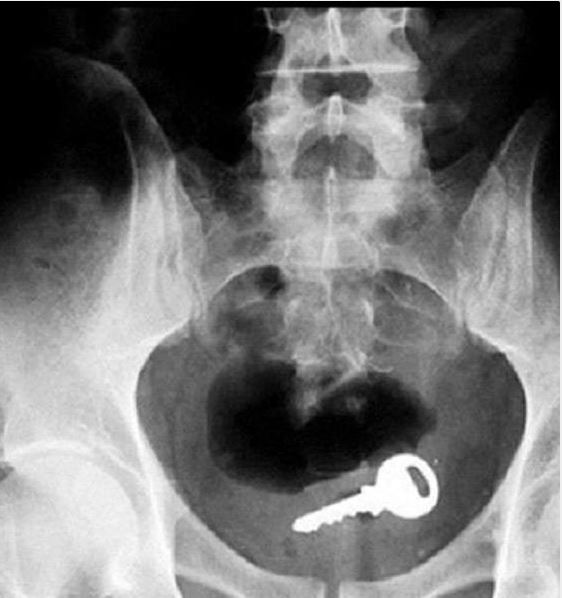

Doktorların görüp yok artık bu nasıl mümkün olur dedikleri röntgen filmleri..

Doktorluğun zor bir meslek olduğu malum. Üstelik bu mesleğin icra ederken bazı zamanlar öyle vakalar ortaya çıkmış ki, doktorlar bile anlamlandırmakta zorluk çekmişler.